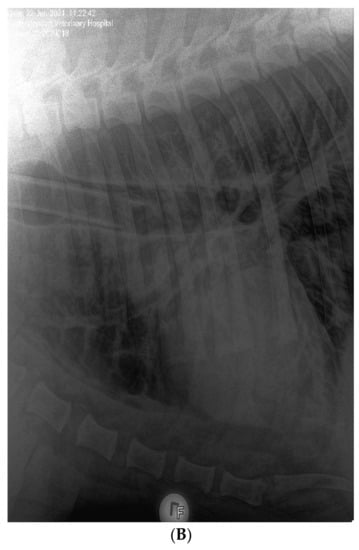

3.1. Clinical Features of SARS-CoV-2 Infection in Pumas and Lions